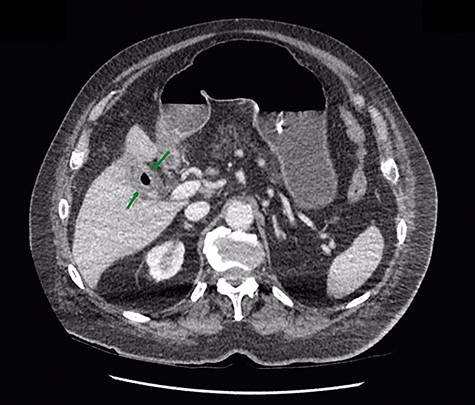

An 81-year-old gentleman presented to the emergency department with a 2-day history of vomiting, central abdominal pain and distension. He had no prior abdominal surgeries, but was waiting for an elective cholecystectomy for chronic cholecystitis. On examination, his abdomen was distended, with mild central abdominal tenderness and no evidence of umbilical or groin hernia. Blood tests were unremarkable except for mild acute kidney injury secondary to dehydration. His plain abdominal X-ray showed dilated small bowel loops (Fig. 1), consistent with a developed SBO. Given the scenario of SBO in a virgin abdomen, a computed tomography (CT) of abdomen was performed, which confirmed the diagnosis of SBO with the transition point being at close proximity to the gallbladder.

Given that the patient was clinically well, he was managed conservatively overnight with a nasogastric tube and intravenous fluid therapy. The CT scan was closely reviewed by the surgical team the following day and noted the presence of gas within the gallbladder, which was not commented upon by the radiologist (Fig. 2). Furthermore, SBO transition point appeared to be in the distal ileum, where a 3-cm “soft tissue” mass was seen (Fig. 3). His previous CT scan that diagnosed his chronic cholecystitis demonstrated a 3-cm gallstone within the gallbladder, which was not seen on the current CT. The findings of gas within the gallbladder in the setting of SBO and a mass of similar size to the known gallstone raised the suspicion for gallstone ileus. The patient then underwent a laparotomy and enterotomy for a 43-mm gallstone impacted in the distal ileum (Fig. 4). Apart from an episode of ileus, he made a full recovery post-operatively and was discharged home, with an outpatient follow-up in the surgical clinic.